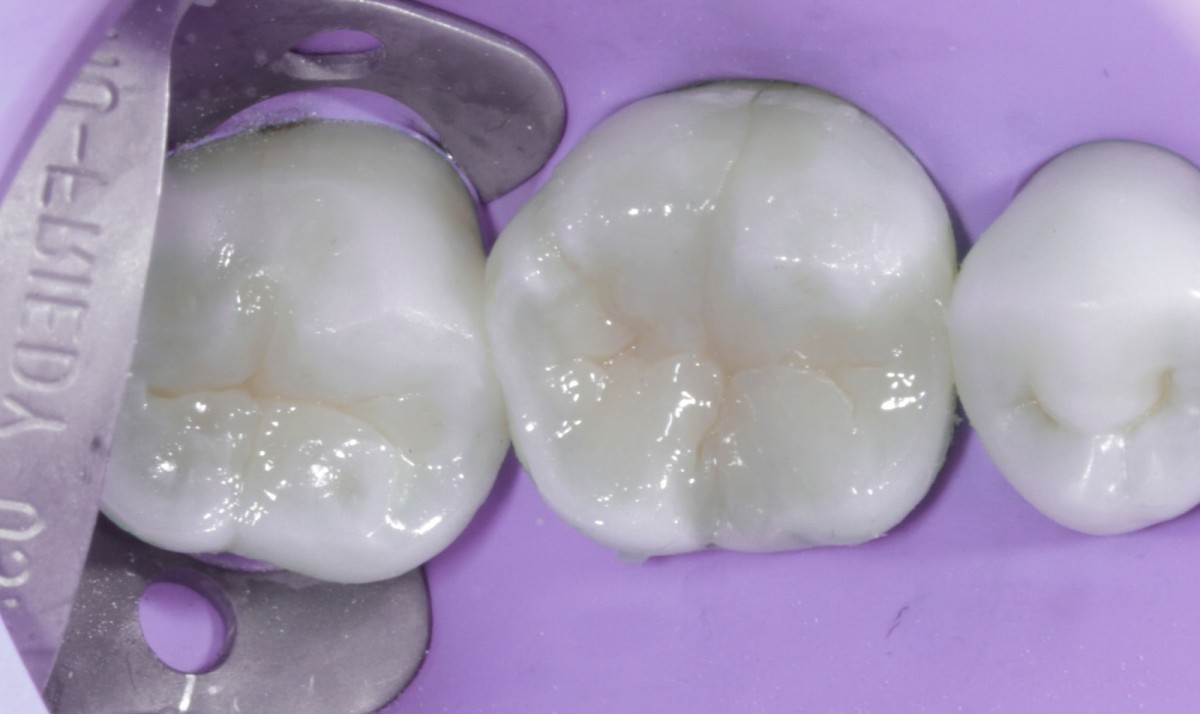

During the visit, consisting of the physical examination and instrumental examinations such as radiographs bitewings, thermal tests and compression tests (to exclude the presence of typical symptoms of a crack) at the level of the fourth quadrant, she has: amalgam restoration on dental element 4.6 associated with primary mesial caries and primary occlusal caries on 4.7.

The quadrant is rehabilitated through direct composite procedures.